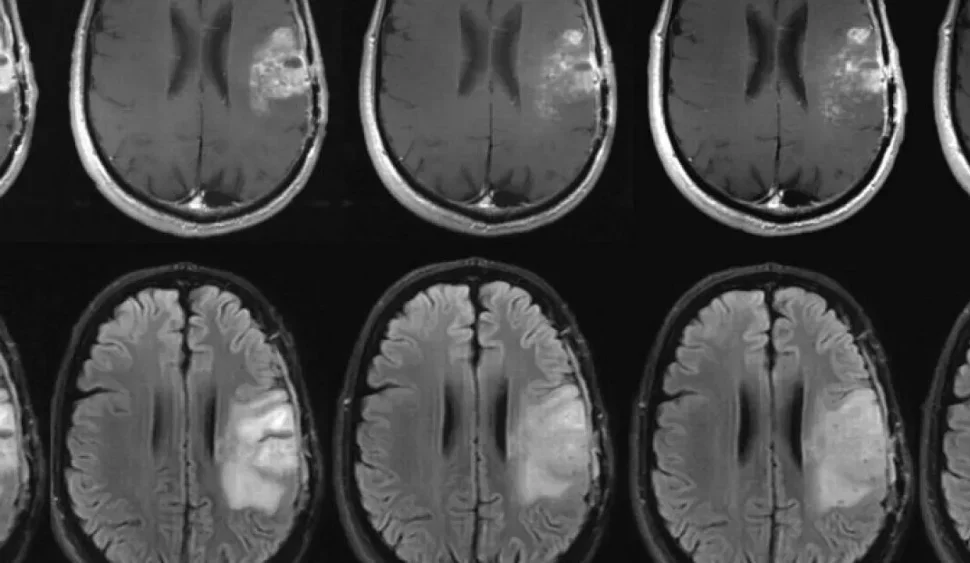

- Görüntüleme Yöntemleri: Hipofiz bezinin durumunu değerlendirmek için manyetik rezonans görüntüleme (MRG) veya bilgisayarlı tomografi (BT) gibi görüntüleme yöntemleri kullanılır.